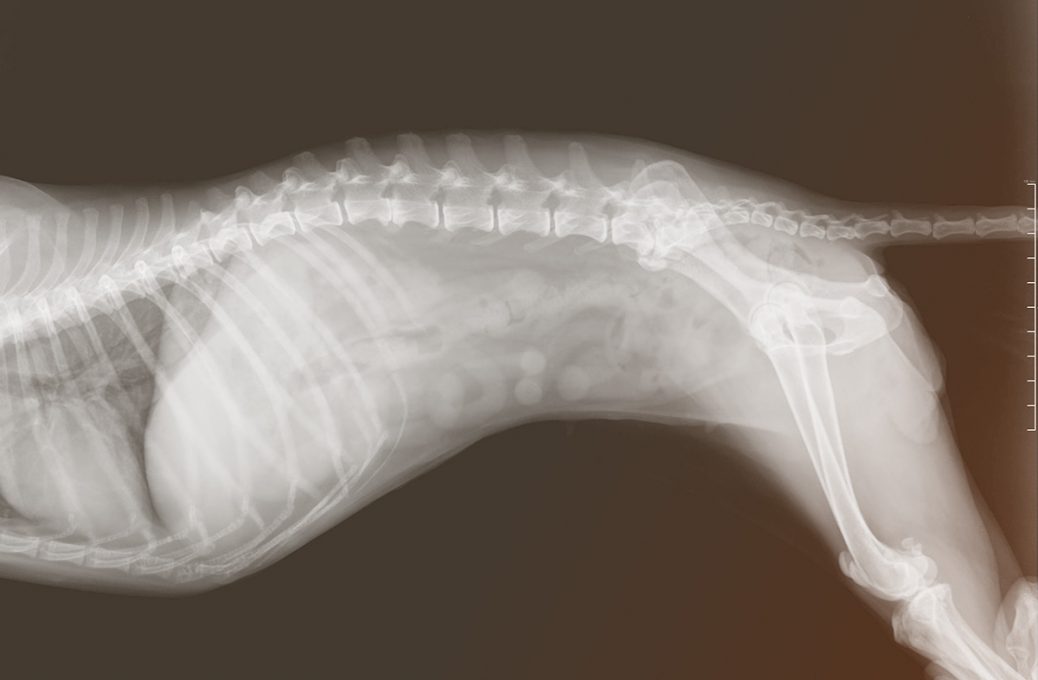

Das Zentrum des Körpers hat eine extrem wichtige Stütz- und Haltefunktion für den Körper, die zum Teil sehr große Belastungen mit sich bringt. Durch ungünstige Bedingungen der Umgebung, durch Bewegungsmangel und unzureichendes Training der tiefen Rumpfmuskulatur, entstehen häufig Gelenk- und Rückenprobleme infolge von Blockaden, Fehl- und Kompensationshaltungen, die das Risiko für Sekundärschäden erhöhen, z. B. Kissing Spines beim Pferd oder Sehnen- und Gelenkschäden, beim Hund häufig Bandscheibenvorfälle. Häufig entwickeln sich bei Pferden und Hunden auch Probleme mit dem Kniegelenk oder mit der Kniescheibe aufgrund von Blockaden und muskulären Defiziten im Bereich der Lendenwirbelsäule und des Beckens.

An der Wirbelsäule gibt es beim Pferd ca. 200 Gelenke (Variationen je nach Tierart), die die Längsbiegung, die Streckung und die Beugung der Wirbelsäule ermöglichen. Diese Beweglichkeit ist notwendig, damit sich ein Tier taktrein bewegen und Hindernisse überwinden kann. Man könnte im weitesten Sinne auch den Vergleich zu einem Stabhochspringer herstellen. Der Stab nimmt die kinetische Energie des Springers auf und katapultiert den Hochspringer über die hoch gelegene Stange.

Beim Tier, v.a. beim Pferd, entsteht die kinetische Energie vor allem in der Hinterhand, das Becken überträgt dann die Kraft auf die Wirbelsäule, die den Körper nach vorne schiebt. Sowohl beim Hochsprung wie auch beim Tier müssen die Wirbelsäule, bzw. der Stab eine gewisse Flexibilität bei gleichzeitiger Stabilität besitzen. Beim Tier entsteht diese notwendige Beweglichkeit durch die 200 Gelenke, die sich entlang der Wirbelsäule zwischen den Wirbeln befinden. Die notwendige Stabilität bekommt sie dadurch, dass die Wirbel gleichzeitig eng miteinander verzahnt sind, so dass für jeden einzelnen Wirbel nur ein sehr kleiner natürlicher Bewegungsspielraum vorhanden ist. Die Gesamtbeweglichkeit entsteht über die Summe der einzelnen Bewegungsspielräume der Wirbelgelenke.

Je größer und schwerer ein Tier ist, desto stabiler muss die Wirbelsäule sein. Denn wenn die Beweglichkeit bei einem schweren Tier groß wäre, könnte die Energie nicht effizient aus der Hinterhand, über das Becken auf die Wirbelsäule übertragen werden.

Die Wirbelsäule würde mit einem Gewicht von ca. 20-30 kg seitlich vor dem großen Gewicht des Körpers wegbiegen (je nach Körpergröße 100-900 kg, Mini-Shetty bis Kaltblut) und könnte den Körper nicht effizient nach vorne schieben, sondern die kinetische Energie würde dann aufgrund der Instabilität in den Seitwärtsbewegungen verloren gehen. Das heißt der Bewegungsspielraum der einzelnen Wirbelgelenke ist bei kleinen, leichten Tieren viel größer (vgl. Seit-Beweglichkeit der Wirbelsäule beim Hund, Katze und Pferd).

Die Wirbelsäule bildet den „Leitungskanal“ und ein vollständig umgebendes knöchernes Schutzgerüst für das Rückenmark. Beidseits der Wirbelsäule treten zwischen den Wirbeln die Spinalnerven hindurch, die das zentrale Nervensystem mit den Organen und Muskeln in der Peripherie verbinden. An diesen Austrittstellen liegt der Ansatzpunkt der Chiropraktik, wenn die Beweglichkeit von Wirbeln eingeschränkt ist, bzw. wenn eine „Blockade“ vorliegt, wie man umgangssprachlich sagt.